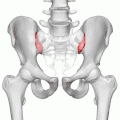

Крестцово-подвздошные суставы (левый и правый) показаны красным